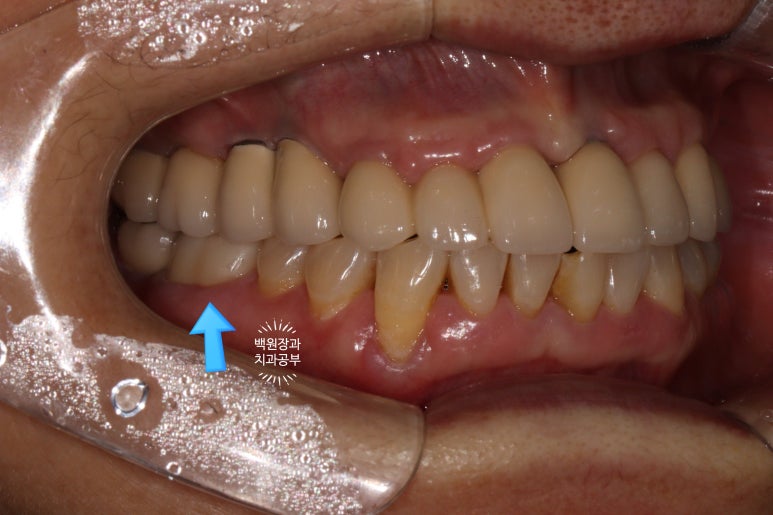

치아의 길이가 너무 짧지 않았기 때문에, 잇몸 성형을 해주지 않아도 되는 경우였어요.

옆에서 보았을 때도 모양이 깔끔합니다.

저렇게 깎여져 있는 채로 집에 가실 수 없죠!

임시치아를 제작하여 접착 후 귀가하시게 되는데요,

보통 지르코니아 크라운을 제작하는데 일주일 정도 소요됩니다.

2차 충치가 깊었기 때문에, 그 1주일동안 별다른 증상이 없는지 평가해보기 위해 임시치아를 제작해 드리는 것이에요. 가만히 있어도 통증이 있거나 너무 시리시면 불가피하게 신경치료를 해야할 수 있기 때문입니다.